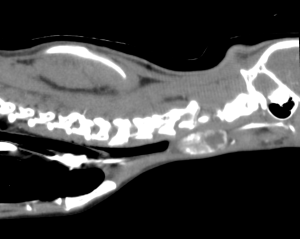

外科的治療は、投薬困難や食事管理ができない場合、甲状腺腫瘍が疑われる場合に選択される治療法です。基本的には原因となる方の甲状腺を摘出することで、ホルモン値は正常化しますが、両側性の場合は2回に分けて両方摘出する場合もあります。また、慢性腎臓病の程度によっては、内科的治療の方が適切な場合もあります。

今回治療させて頂いた猫ちゃんは、甲状腺が腫瘍化し、数値が不安定になってきたため、甲状腺摘出を行いました。術後2日で退院し、無治療で数値は安定している状態です。